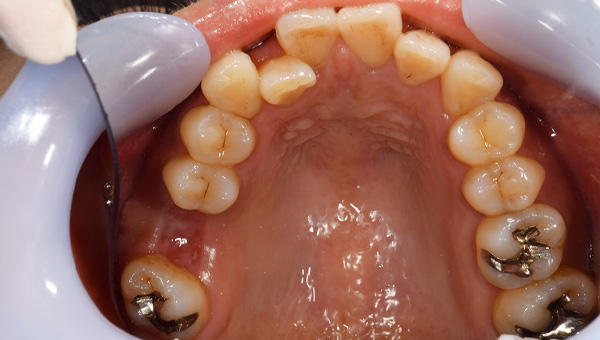

初診時の口腔内

説明:

初診時の口腔内です。かぶせ物があり、一見虫歯とはわからないです。

初診時のパノラマ

初診時のパノラマです。左下の一番奥の歯が虫歯になっているのがわかります。